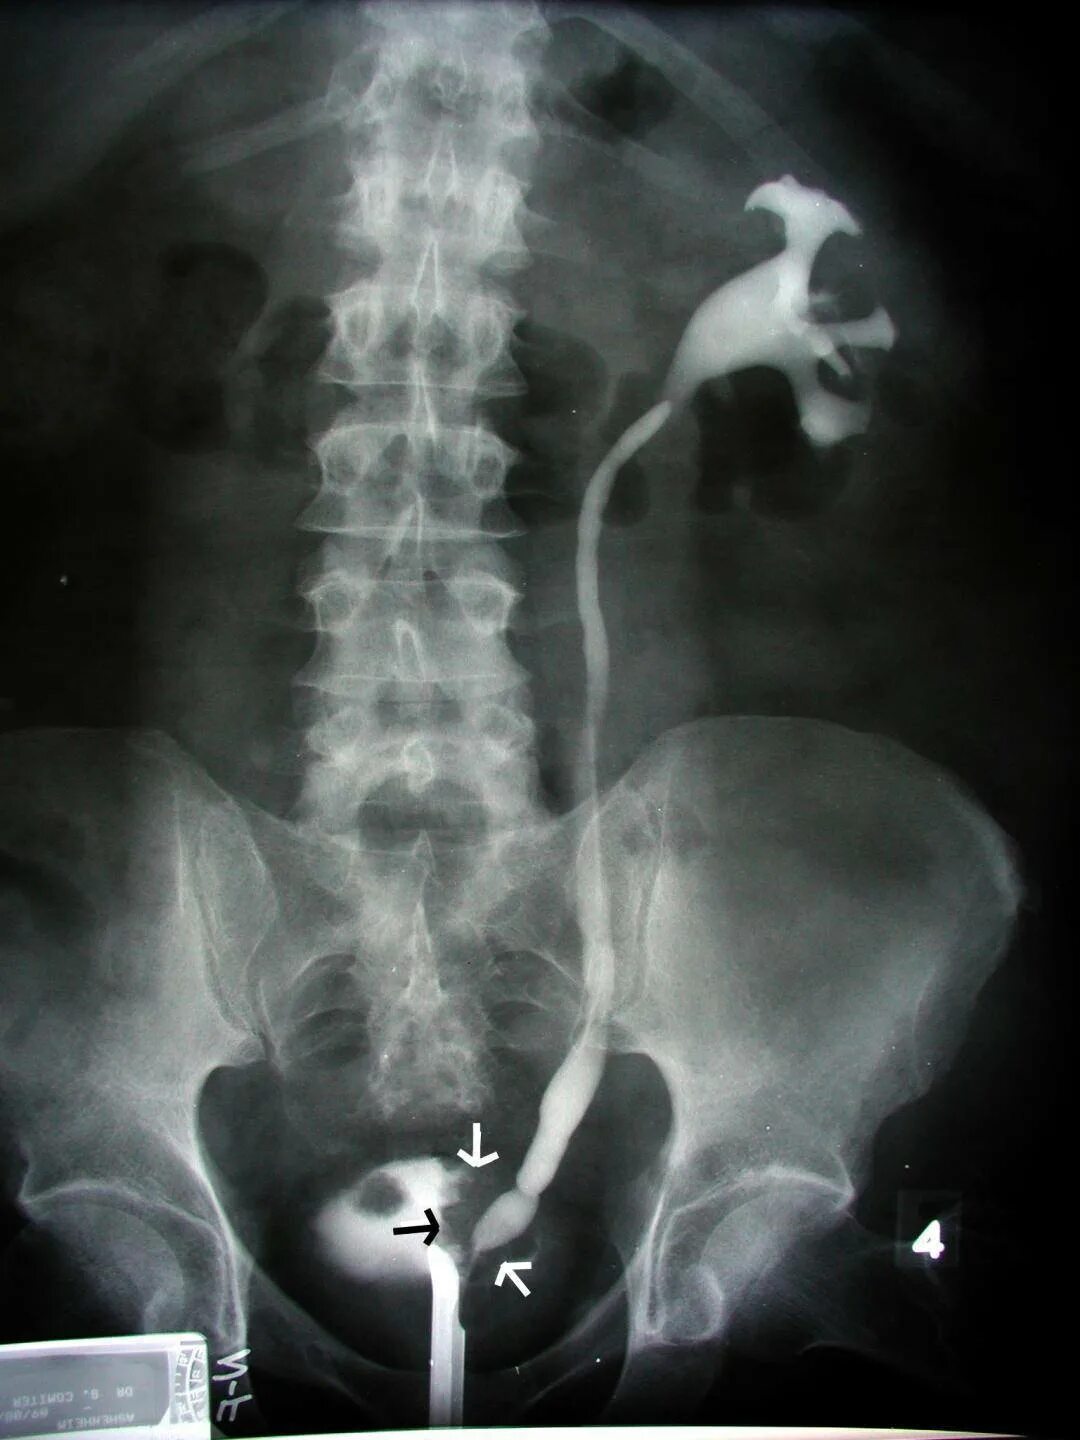

Как делается урография